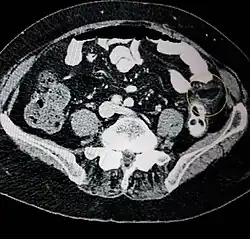

Epiploic appendagitis in computed tomography.

Ultrasound and CT scans are the normal means of positive diagnosis of epiploic appendagitis. Ultrasound scans show "an oval, non-compressible hyperechoic mass with a subtle hypoechoic rim directly under the site of maximum tenderness".[4] Normally, epiploic appendages cannot be seen on CT scan.[4] After cross-sectional imaging and the increased use of abdominal CT for evaluating lower abdominal pain, EA is increasingly diagnosed. Pathognomonic CT scan data represent EA as 2–4 cm, oval shaped, fat density lesions, surrounded by inflammation. Contrasting with diverticulitis findings, the colonic wall is mostly unchanged.